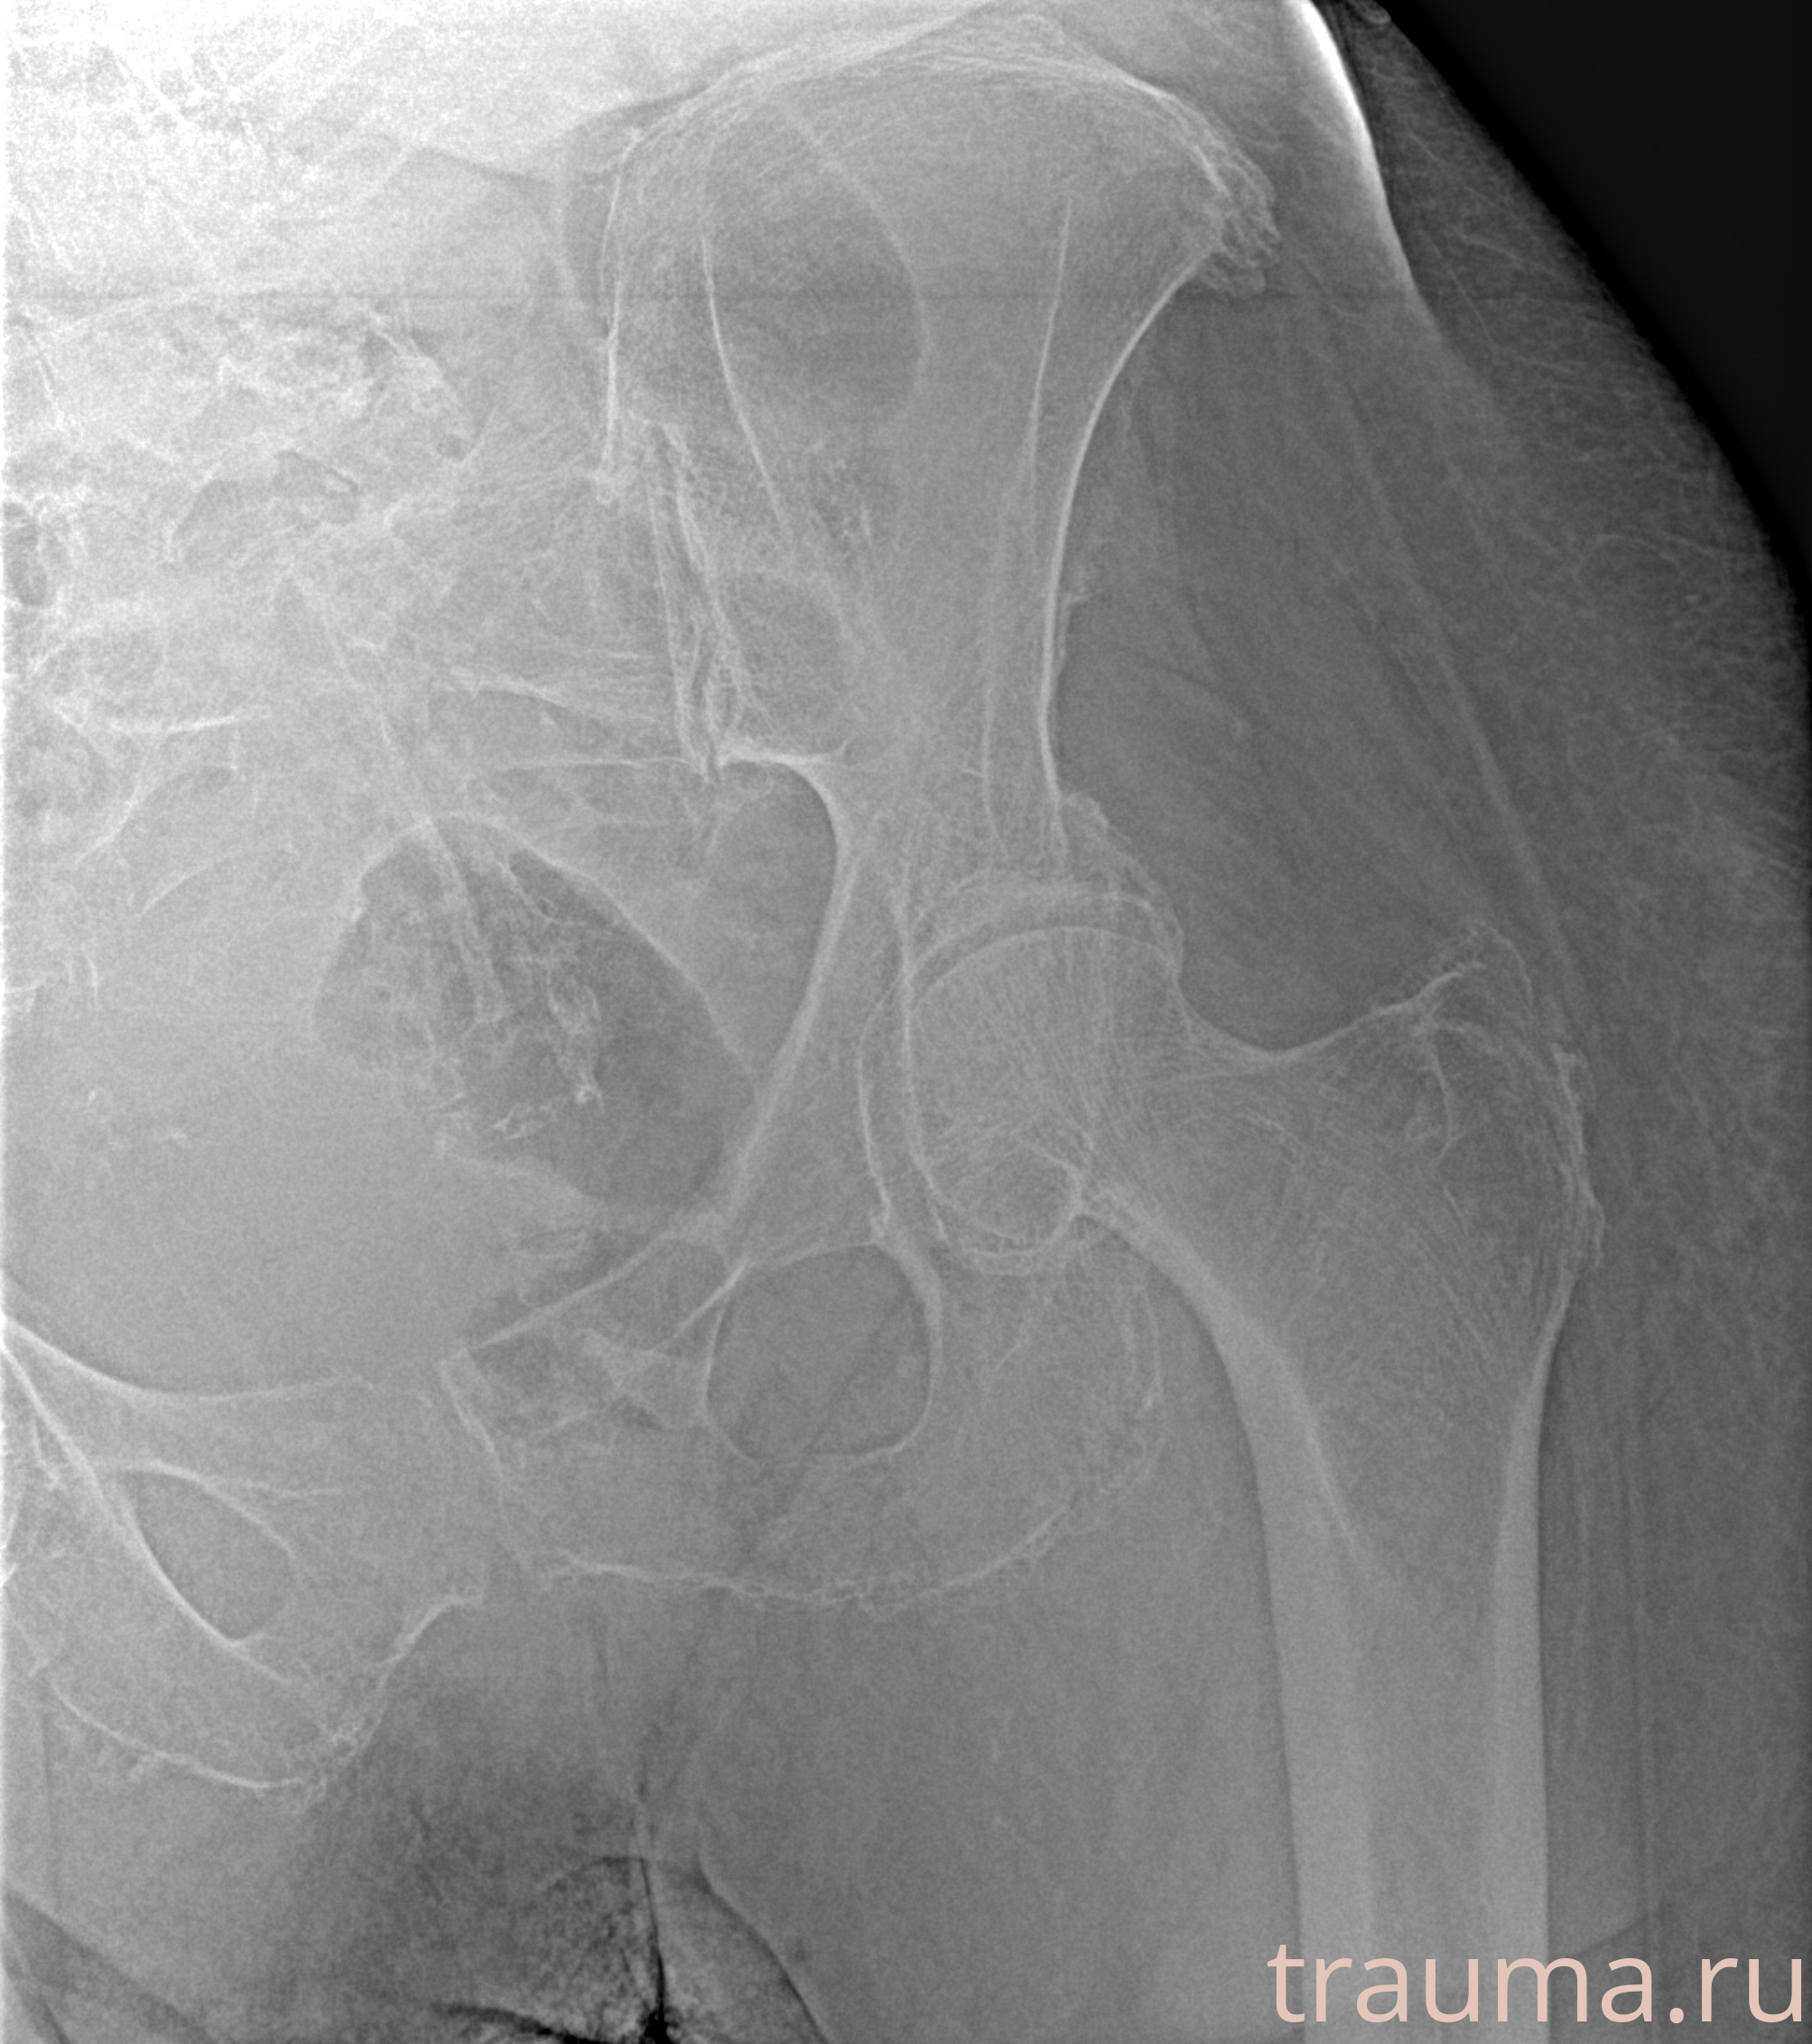

Рентгенограммы

Рентген на дому: по вашему адресу приезжает врач-рентгенолог, травматолог-ортопед с мобильным рентгеновским аппаратом, проводит диагностику травмы или заболевания, делает необходимые рентгенограммы, дает рекомендации по дальнейшему лечению. Получить качественные снимки в домашних условиях возможно благодаря уникальной методике, разработанной МосРентген Центром для института  Склифосовского